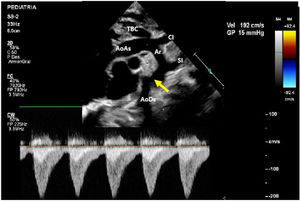

A los 8 días de vida el paciente presenta deterioro hemodinámico con bajo gasto, tras iniciar soporte inotrópico con milrinona (1 μg/kg/min) se realiza un nuevo ecocardiograma en el cual se evidencia un arco aórtico ligeramente elongado con los siguientes diámetros: 6mm en la aorta ascendente, 4mm a nivel del cayado y 3mm en el istmo con un gradiente de 15mmHg con extensión diastólica y pulsatilidad disminuida en la aorta abdominal (fig. 2). Ante la progresión de la CoA y el deterioro clínico del paciente, se decidió tratamiento quirúrgico con el diagnóstico de CoA aislada.

Muestra la ecocardiografía a los 8 días de nacimiento con progresión del gradiente a nivel de la coartación; la flecha señala la coartación de aorta.

AoAs: aorta ascendente; AoDs: aorta descendente; Ar: arco aórtico; CI: arteria carótida izquierda; SI: arteria subclavia izquierda; TBC: tronco braquiocefálico.